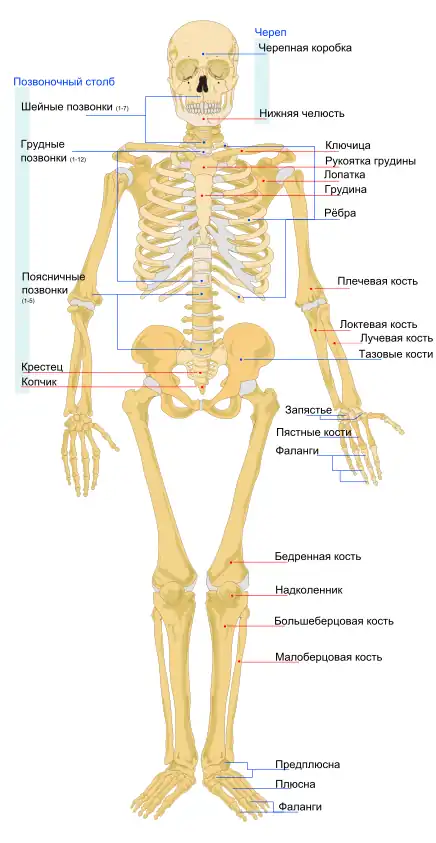

- Скелет человека